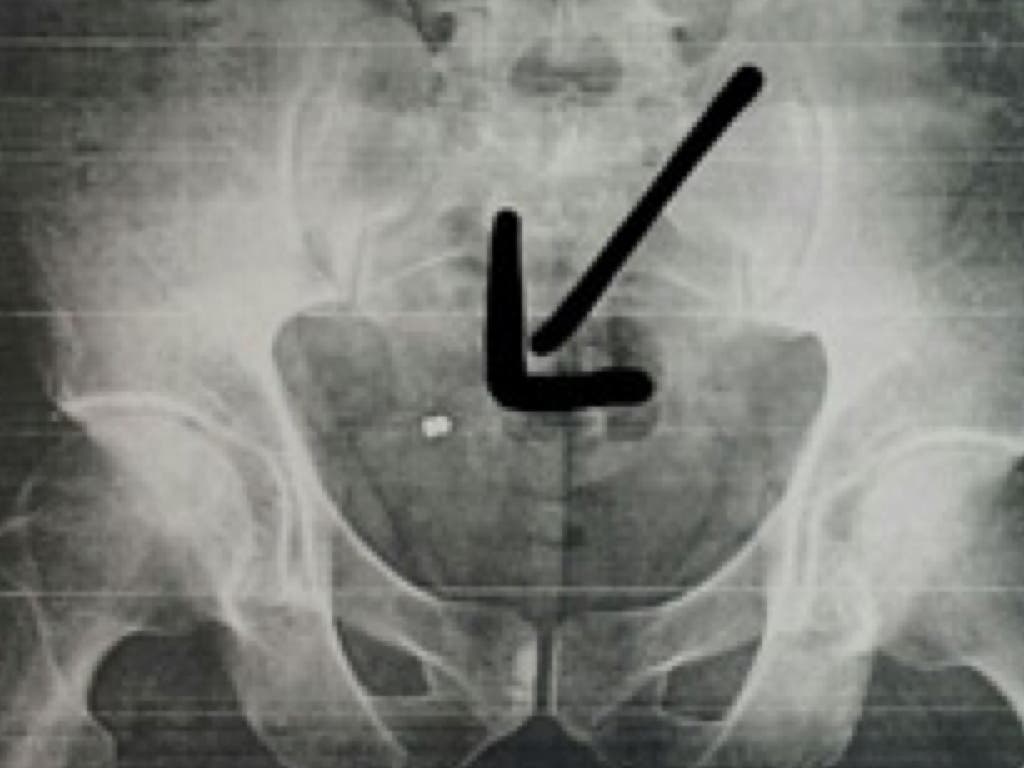

Fue en su casa cuando se dio cuenta de que tenía un orificio, volviendo al día siguiente a la mutua donde ya sí le hicieron una radiografía y comprobaron que tenía un perdigón incrustado en su nalga derecha, como se puede ver en la imagen que publicamos a continuación, cedida por El Heraldo del Henares.

El empleado municipal fue derivado al Hospital de Fremap en Majadahonda donde, una semana después, será operado este jueves para poder extraerle el perdigón.